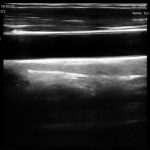

El ecógrafo inalámbrico portátil de alta rentabilidad es la herramienta ideal para estudiantes de medicina, enfermería, kinesiología, veterinaria y carreras del área de la salud. Gracias a su bajo costo, es accesible como la compra de un teléfono celular, permitiendo que más personas puedan entrenar con tecnología real sin depender de los equipos institucionales.

Es una herramienta ideal para quienes buscan formarse en ecografía de manera práctica, económica y accesible, brindando imágenes de buena resolución para entrenar la identificación de estructuras anatómicas, técnicas de exploración y procedimientos básicos.

Ultrasonido Doppler color súper rentable: ideal para estudiantes y profesionales que buscan alta relación calidad-precio.

Exploración Doppler color en clínicas y punto de atención.

Monitoreo de vasos y flujo sanguíneo en entornos clínicos y educativos.